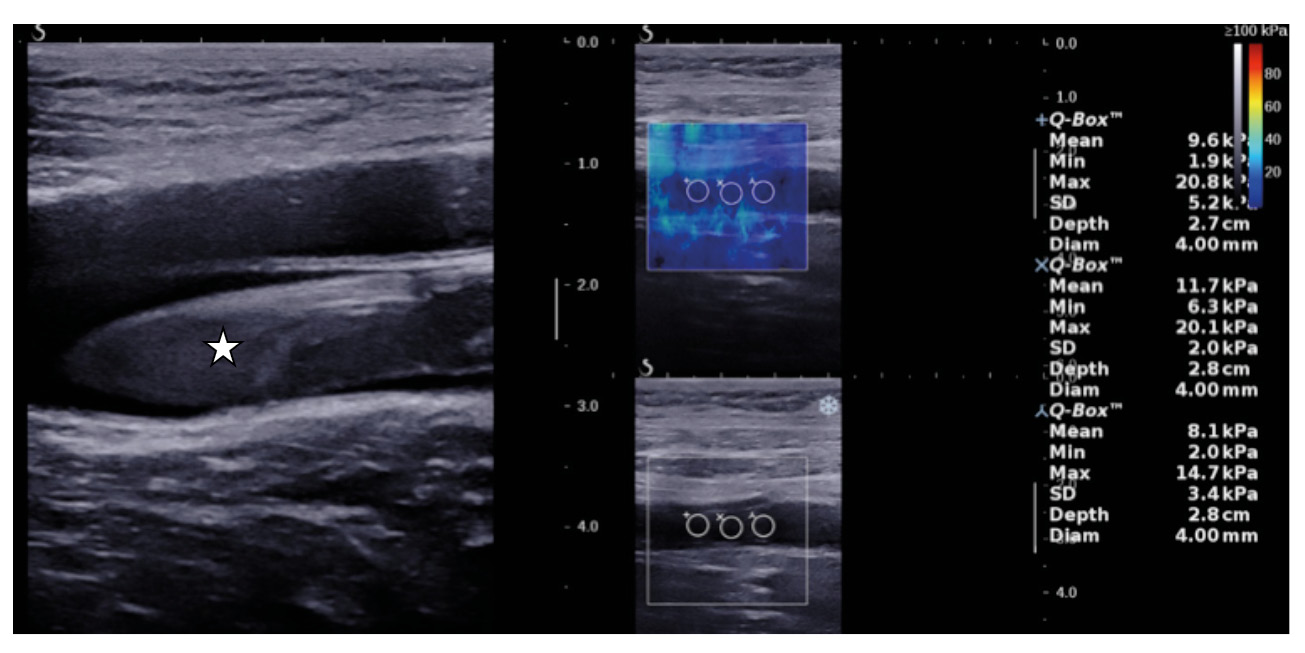

В первые сутки поступления в стационар всем пациентам выполняли дуплексное сканирование вен нижних конечностей с эластографией сдвиговой волной на аппарате Aixplorer (Supersonic Imagine, Франция). При исследовании ПВ использовали конвексный датчик (1–6 МГц); БВ, подколенной (ПКВ) и заднебольшеберцовых вен (ЗББВ) – линейный датчик (2–10 МГц). Для проведения эластографии сдвиговой волной после визуализации просвета вены, содержащей тромб, датчик фиксировали без компрессии. Поскольку растущей частью тромба является его верхняя граница, контрольный объем (Q-box) устанавливали при тромбозе ПВ на проксимальную часть тромба ПВ; при тромбозе БВ – на проксимальную часть тромба БВ. Измерения в средней части тромба ПКВ и ЗББВ проводили всем пациентам. Диаметр Q-box подбирали на 1–2 мм меньше размера тромба. По результатам трехкратного измерения модуля Юнга, отражающего жесткость тромба, в окнах одинакового размера программа эластографии сдвиговой волной в полуавтоматическом режиме выдает средние значения в килопаскалях (кПа) (рис. 1).

Рис. 1. Ультразвуковое изображение тромба бедренной вены: слева – В-режим, справа – определение жесткости тромба с указанием значений модуля Юнга в трех измерениях сиспользованием эластографии сдвиговой волной